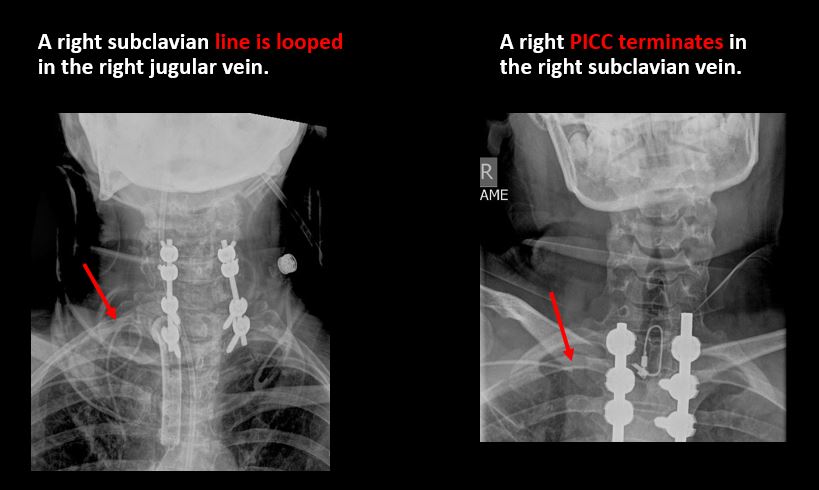

Section 1 Submit Findings C442 Findings Technique The craniocervical junction and/or C7-T1 are not entirely included on the exam. Yes No The exam is over or under penetrated. Yes No The exam is limited by overlying structures, bones or soft tissues, body habitus, patient positioning, support devices, or motion. Yes No Prevertebral and paravertebral soft tissues The soft tissues anterior to C1-C7 are widened or the prevertebral fat stripe is not seen. Yes No The paravertebral soft tissues are abnormally widened. Yes No N/A There is calcification, foreign body, abnormal air, or other abnormal density in the prevertebral or paravertebral soft tissues. Yes No Spinal alignment The distance between the basion and the posterior axial line is > 12 mm. Yes No The distance between the basion and the tip of the dens is > 12 mm. Yes No The atlanto-axial joint distance is > 2 mm on the lateral view. Yes No The distance between the dens and the lateral masses of C1 is abnormally asymmetrically widened on an odontoid or AP view. Yes No N/A The lateral mass(es) of C1 abnormally override(s) the articular pillar(s) of C2 on an odontoid or AP view. Yes No N/A The anterior vertebral body line, posterior vertebral body line, articular pillar line, and/or spinolaminar line is/are abnormal. Yes No The articular pillars or lateral masses, lamina, or other posterior elements are rotated or displaced into the spinal canal or the interlaminar clear zone of the spinal canal. Yes No The visualized spinous processes are malaligned on the AP view or distracted on the lateral view. Yes No There is reversal or straightening of the normal lordosis or abnormal angulation/curvature or motion of the cervical spine on frontal, lateral, flexion and/or extension views. Yes No Vertebral bodies, posterior elements, and base of skull There is a fracture or deformity of the base of the skull or occipital condyles. Yes No There is a fracture or deformity of the anterior or posterior arch of C1. Yes No There is a fracture or deformity of the lateral mass(es) of C1. Yes No There is a fracture or deformity of the dens or C2 vertebral body. Yes No There is a fracture or deformity of the pars interarticularis/articular pillars or other posterior elements of C2. Yes No There is a fracture or distraction of a C3-T1 vertebral body, transverse or spinous process, or other posterior element. Yes No There is evidence of an end plate avulsion or other fracture. Yes No There is displacement of a fracture fragment into the soft tissues, spinal canal, or interlaminar clear zone of the spinal canal. Yes No There is anterior wedging or compression of a vertebral body or end plate. Yes No There is evidence of an aggressive disease process manifest as a lytic, sclerotic, or destructive abnormality of a vertebral body, end plate, pedicle, lamina, articular pillar, transverse or spinous process. Yes No There is focal or diffuse abnormal mineralization. Yes No Disc spaces and facet joints There is distraction or focal widening of a disc space. Yes No There is anterolisthesis, retrolisthesis, subluxation, or rotational abnormality of a disc space. Yes No There is widening, rotational abnormality, or displacement of facets at any motion segment (e.g. locked or jumped, perched facets, or fracture dislocation). Yes No There is disc space narrowing with or without erosive or sclerotic changes of the end plates other than from degenerative change. Yes No There is facet joint narrowing or sclerosis other than from degenerative change. Yes No Additional soft tissues and bones (neck, airway, upper thorax, ribs) The included maxillofacial region, thoracic spine, ribs, or other bones of the upper thorax are abnormal. Yes No There is air or a foreign body or other abnormality in the soft tissues of the lower head, neck or upper thorax. Yes No There is an apical mass, thickening, pleural cap or effusion, or pneumothorax. Yes No N/A The airway is narrowed or displaced. Yes No There are post surgical changes of the bones or soft tissues of the lower head, neck, or upper thorax. Yes No There is an abnormality or complication of post-surgical hardware. Yes No N/A There are support lines or tubes in an abnormal position. Yes No Other findings There are degenerative changes or other existing conditions that might be contributing to symptoms which can or should be further evaluated non-emergently. Yes No